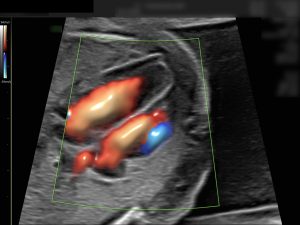

Mit der Feindiagnostik lassen sich alle sichtbaren Organe prüfen, das Herz und die Durchblutung in den Gebärmutterarterien kontrollieren. Ein Ultraschall kann jedoch nie alle körperlichen oder chromosomalen Auffälligkeiten ausschließen.